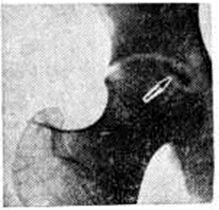

Остеонекроз (osteonecrosis; греческий osteon кость + некроз) — омертвение участка кости. Возникает в результате травмы, воспаления, сосудистых нарушений, функциональный перегрузки кости и другие При Остеонекроз наступает гибель остеоцитов; межуточное вещество кости при этом, как правило, сохраняется. В дальнейшем зона Остеонекроз отделяется грануляционной и соединительной тканью. Минеральный состав кости в области Остеонекроз обычно не изменяется, однако возрастает относительное количество плотных элементов. На рентгенограмме зона Остеонекроз отделяется полоской просветления и выглядит более плотной, чем окружающая костная ткань, которая сохраняет обычный вид или становится несколько порозной (рисунок). На границе участка Остеонекроз и полоски просветления ход костных балок прерывается.

Рис

Рентгенограмма правого тазобедренного сустава при остеонекрозе: некротический участок (указан стрелкой) в головке бедренной кости отделен от окружающей костной ткани полоской просветления.